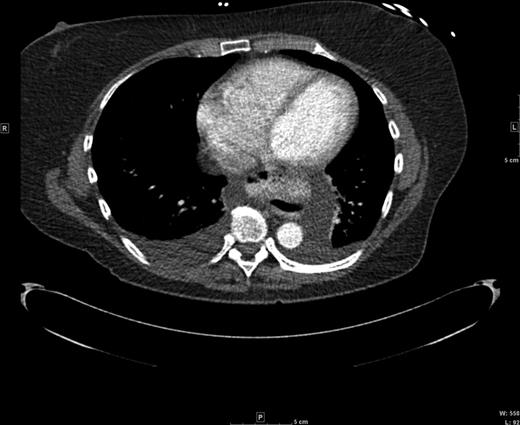

A 60-year-old female with a long-standing gastroesophageal reflux disease and known type III paraesophageal hernia presented to the emergency department with acute epigastric pain, dysphagia and vomiting. She noted a 1-month history of progressive dysphagia as well. Computed tomography (CT) revealed a large paraesophageal hernia with significant surrounding fluid concerning for incarceration (Figs 1 and 2). Owing to these findings and her discomfort, emergent laparoscopic repair of her paraesophageal hernia was recommended.

Axial CT view of the paraesophageal hernia and mediastinal fluid.